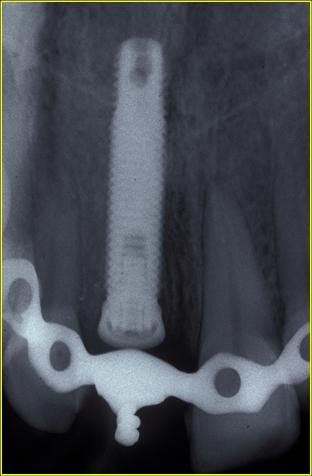

Radiograficamente è visibile il trattamento endodontico dell’incisivo laterale sinistro coinvolto anch’esso nel trauma. Sono visibili inoltre i dispositivi ortodontici necessari pe la sua estrusione al fine di recuperare l’ampiezza biologica, ovvero al fine di mantenere tre millimetri di tessuto dentale sano oltre il margine gengivale

Immagini radiografiche successive è possibile seguire negli anni l’evoluzione del dente reimpiantato. Nel corso degli la radice dell’incisivo centrale è andata in contro ad un progressivo riassorbimento per un atteso fenomeno di anchilosi.

L’anchilosi è un processo biologico infiammatorio che si verifica una volta che le fibre del legamento parodontale sono andate in necrosi e la superficie del cemento che ricompre la radice viene in contatto diretto con l’osso alveolare. In questa circostanza si attiva nei macrofagi una differenziazione in senso osteoclastico e dentino clastico che in pochi anni, talvolta in pochi mesi, porta al completo riassorbimento della radice e quindi alla sua scomparsa

Visione clinica del Maryland bridge cementato con tecnica adesiva ed immagine tomografica tridimensionale per valutare lo spessore bucco palatale utile all’inserimento dell’impianto che fu valutato come sufficiente benchè esiguo. A tal proposito deve essere sottolineato che la letteratura consiglia, quando è disponibile un volume di osso residuo utile all’inserimento di un impianto, di evitare tecniche di innesto osseo in quanto un aumento dei volumi ossei non migliora la prognosi estetica (3)

Sono necessarie relativamente a questo caso alcune considerazioni. In primo luogo la decisione di procedere comunque al reimpianto del dente avulso nonostante fossero trascorsi due giorni e fosse pertanto certa la necrosi delle fibre parodontali, è stata premiante in quanto i fenomeni di anchilosi si sono affermati nel corso di circa dieci anni il che ha permesso alla paziente di raggiungere la maturità scheletrica e quindi di poter ricevere un trattamento implanto protesico.